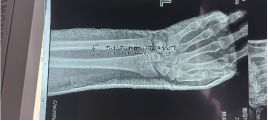

▲近日一则使用五研骨科机器人的手术病例

小腿开放性粉碎骨折

小腿开放性粉碎骨折伴随局部软组织挫伤,骨折断端重叠移位明显。

在成永忠教授的带领下,首次用机器人完成复位并且很好的维持复位效果,微创CO接骨架完成固定!